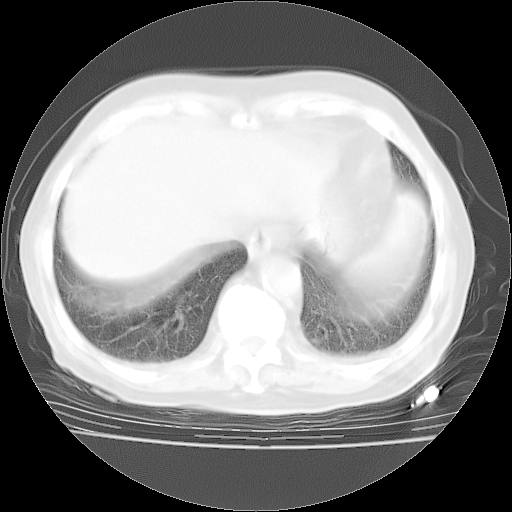

4月28日肺部CT——再次出现类似去年5月9日——透光度降低,“间质性”改变。

4月28日肺部CT——再次出现类似去年5月9日——磨玻璃样、间有“粟粒样”改变。

个人阅读4.14日肺部CT平扫:纵隔窗无异常,但肺窗示:双下肺内、后基底段有片絮状侵润影,部位以后基底段为著,以间质改变为主,呈急性肺泡炎征像,和首次住院影像学有相似之处。仅是个人读片,明日请相关专家再读片哈。其它建议同上。